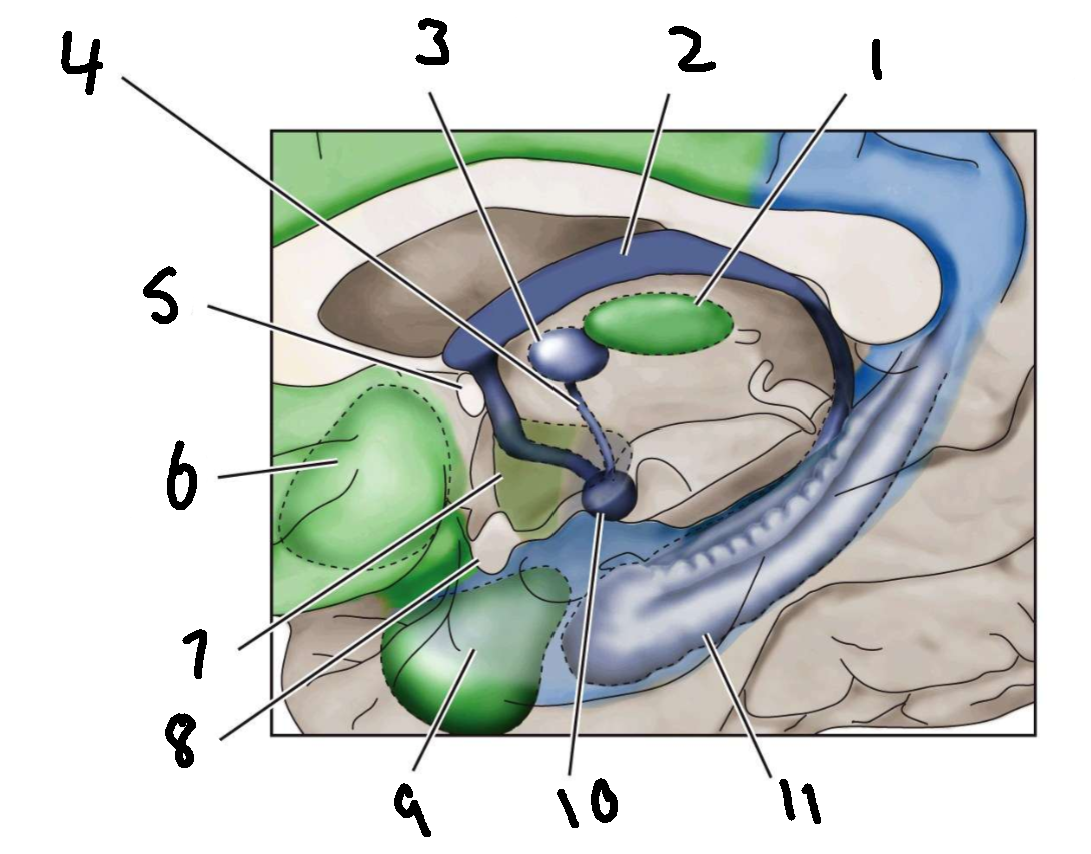

What is 1?

mediodorsal nucleus of the thalamus

What is 2?

fornix

What is 3?

anterior nucleus of the thalamus

What is 4?

mammillothalamic tract

What is 5?

anterior commissure

What is 6?

ventral basal ganglia

What is 7?

hypothalamus

What is 8?

optic chiasm

What is 9?

amygdala

What is 10?

mammillary body

What is 11?

hippocampus